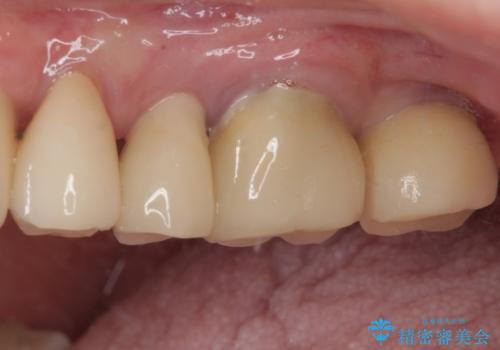

最小の来院回数で短期間で治療を終えることができました。